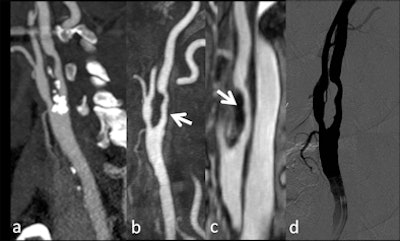

Time-resolved sequences allow the real-time visualization of the contrast medium, which is very useful in diagnosing vascular malformations and fistulas, especially for the analysis of hemodynamic characteristics (feeding arteries and draining vessels) in order to plan the optimal endovascular treatment, commented Catalano. In addition, dynamic sequences may be useful in the evaluation of carotid dissection, and make it possible to visualize abnormal flow dynamics in the false lumen of the affected vessel. Dynamic CT studies are also feasible and can represent a useful addendum to stroke imaging, but these protocols are rarely used in clinical practice because of the high radiation dose, especially if combined with perfusion studies.

| Patient with dissection of brachiocephalic arterial trunk and right common carotid artery. A, B: Time-resolved sequences allow the visualization of an asymmetric transit time of the contrast agent, showing delayed opacification of right common and internal carotid artery compared to the normal left vessels. (Provided by Prof. Carlo Catalano and Dr. Beatrice Cavallo Marincola) |